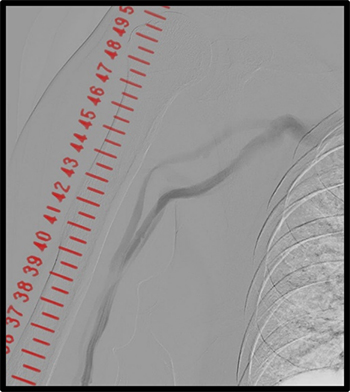

その他、当院で実際に使用した臨床例について示す。(図10、図11、図12)

IGS630_Fukaya_14.jpg図11 下大静脈フィルター